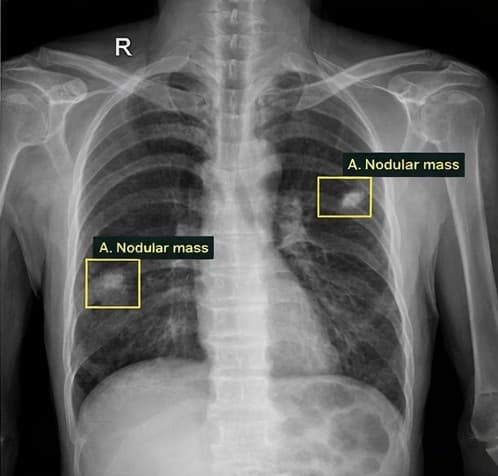

Lung tumor

Tuberculosis

TB | 0.94Sputum collection pending

Tuberculosis | 0.94Sputum collection pending